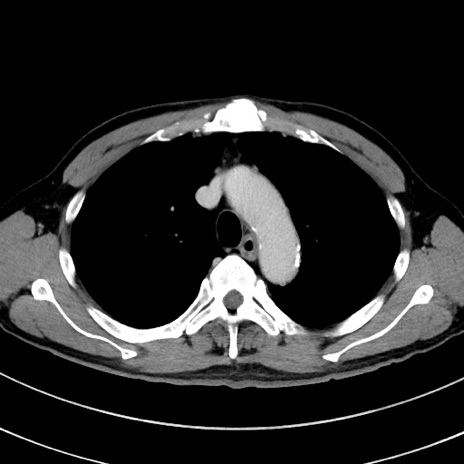

冠状断像

【症例】 60歳代男性

【主訴】 黒色吐物

【現病歴】 4日前から嘔気自覚、2日前の朝食後にも嘔気あり、自分で手で嘔吐反射起こし嘔吐したところ血が混ざっていたため受診。

【既往歴】 5年前汎発性腹膜炎を伴う急性虫垂炎で手術、高血圧、前立腺肥大症、高脂血症

【身体所見】 腹部正中に手術癩痕あり 腹部平坦・軟圧痛なし膨満感あり

【データ】WBC 8400、CRP 4.54